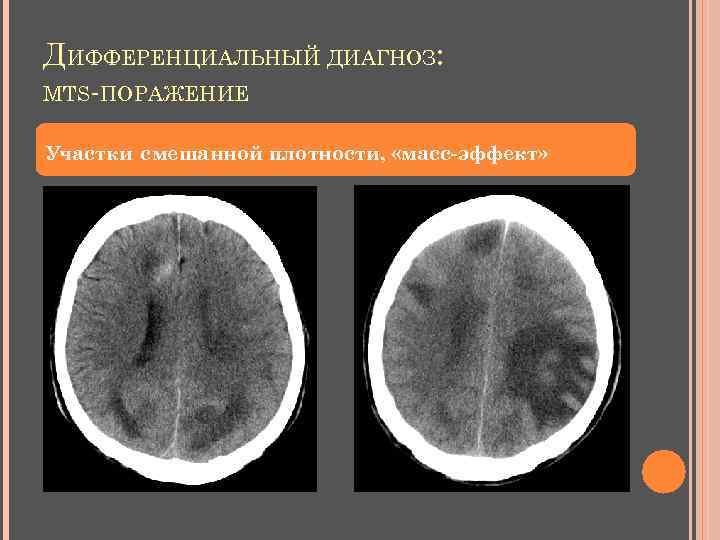

ДИФФЕРЕНЦИАЛЬНЫЙ ДИАГНОЗ: MTS-ПОРАЖЕНИЕ Участки смешанной плотности, «масс-эффект»